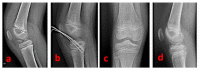

Materials and methods: Standard and patient-specific accessory arthroscopic portals allow for full access to knee visualization and management of concomitant intraarticular lesions. After performing the debridement of the inflammatory tissue and the release of eventual interposed tissues in the fracture site, the tibial eminence avulsion can be reduced by using a less-invasive bone impactor. With the knee flexed to 90°, the fracture fragments are then synthesized (under fluoroscopic control) with three thin Kirschner wires inserted in a proximal-distal direction in a cross-shaped geometry.

Results: This technique allows a fast surgical and hospitalization time, a punctiform arthrotomy, proximal tibial physis preservation, and an early rehabilitation program.